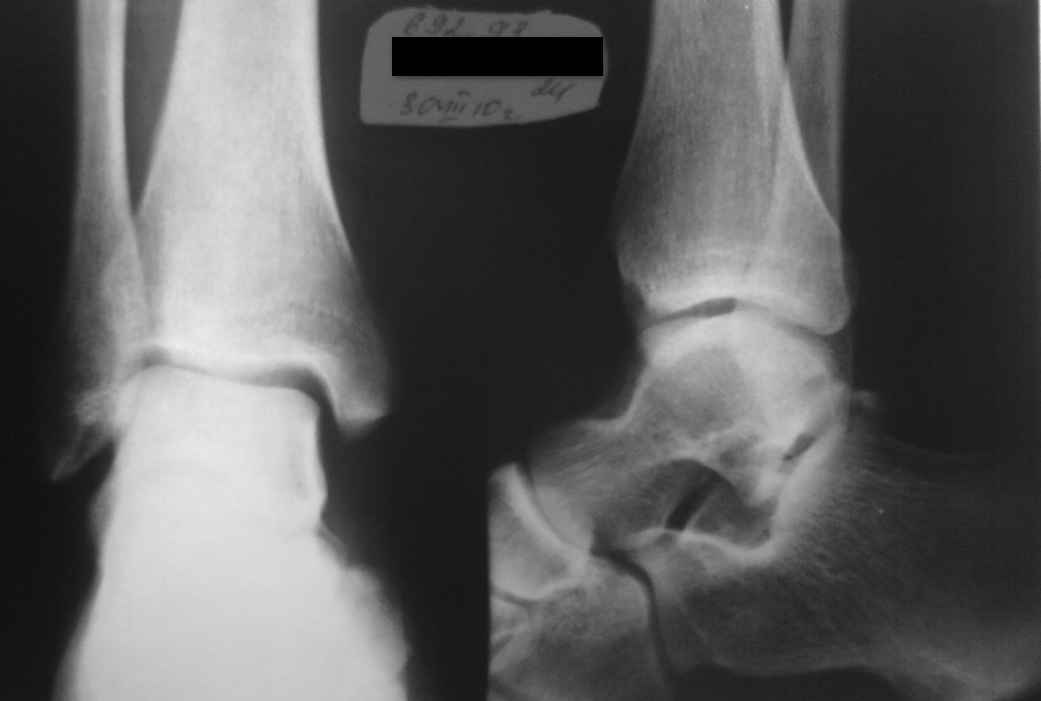

Начну с того что проходил службу в армии с декабря 2008-декабрь 2009 года. Примерно в Июле 2009 года ударили по правой ноге в область голени. В армии этот случай хотел "замять" поэтому ходил с больной ногой. В сан части сказал что подвернул ногу. Как выяснилось после демобилизации (6 месяцев спустя) был перелом малой берцовой кости. Этот диагноз поставили в местном травмпункте, где сделали снимок голени. Снимок я прикрепил. Примерно через неделю после удара я заступал в караул с спрыгивал с кузова грузового автомобиля и видимо преземлился неудачно, т.к. сразу же упал на руки от резкой боли в правой ноге. После этого голеностоп еще больше начал болеть. К сожалению в сан часть я так и не обратился. Так и ходил хромал.Вот уже на протяжении года у меня дискомфорт при ходьбе (чувство натянутости в голеностопе), а также были ночью боли в голеностопном суставе. Появилось чувство деформированности стопы. Дома хожу в мягких тапочках. Очень быстро утомляюсь. Бегать не могу в походы не хожу хотя раньше занимался туризмом. Уже спустя больше 1 года и 2 месяца обратился в травматологическую клинику, где сделали снимок голеностопного сустава и поставили диагноз перелома заднего отростка таранной кости. Ничего не назначали для лечения, Затем я снова обратился в трав пункт нашего города сделали УЗИ и там мне поставили диагноз застарелого разрыва дельтовидной связки, и направили на операцию на ее подшитие, после осмотра глав врачом он сказал что тоже перелом в суставе бал и операцию делать не будут. Затем я уже ездил в город Новосибирск и обратился в областную больницу где поставили диагноз "Неконсолидированного перелома суставного отростка таранной кости и прописал лечение ФИзио таблетки "структум", "мовалис". (прикрепил листок). Контрольная явка через 3 месяца.Пролечился 1 месяц ушло чувство стянутости в голени, чему я рад, но теперь стали болеть связки в голеностопе, а также все равно что мурашки в области пятки, Что делать?